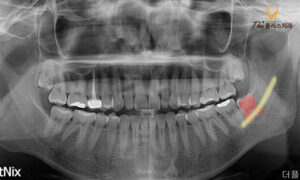

전반적인 엑스레이 촬영 결과,

환자분께서는 위쪽 양옆에 2개,

아래 왼쪽에 1개의 사랑니가 존재하였고,

환자분께서 불편해 하시는

왼쪽 아래의 사랑니는

잇몸뼈에 완전히 매복되어 있는 상태였습니다.

환자분의 왼쪽 아래의 사랑니는

다행히 누워있는 형태는 아니었으나,

치아 뿌리의 형태가 많이 휘어 있어

발치를 진행하는 과정에서

부러질 수 있는 가능성이 있었으며,

아래턱뼈를 가로지르는 하치조 신경관과

거리가 매우 가까운 케이스로

난이도가 높은 편에 속하였습니다.